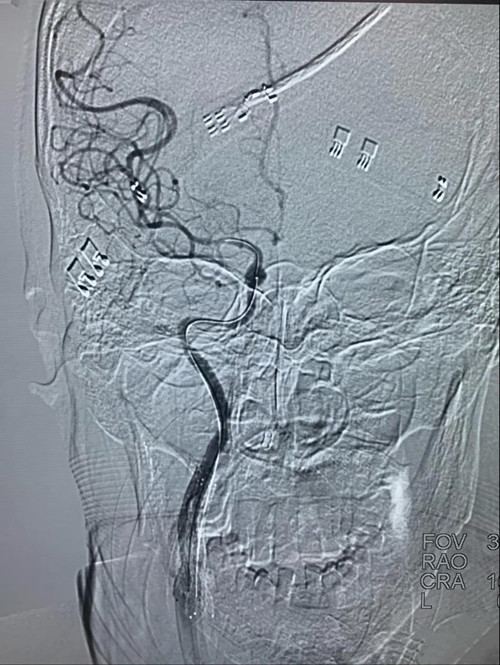

取栓程中,

导丝艰难寻找到闭塞颈内动脉的真腔

微导管进入颈内动脉颅内段

微量造影确认颅内血管闭塞

为快速恢复患者颅内脑组织的灌注血流,抽吸导管在球囊辅助下应用“特洛伊木马”技术将抽吸导管快速通过右颈内动脉闭塞病变送至右侧大脑中动脉闭塞处,进行取栓操作。

取栓操作

抽吸导管到右侧大脑中动脉闭塞处进行取栓操作。